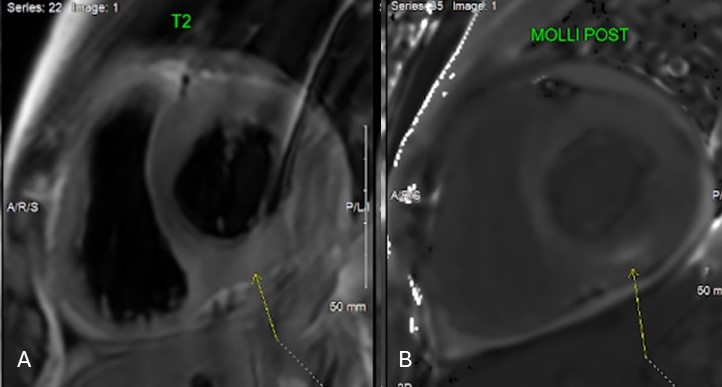

Figure 2: A. T2Weighted image short axis of LV showing increased hyperintensity (arrow). B. Post contrast Modified Look-Locker sequence showing area devoid of contrast uptake (arrow).